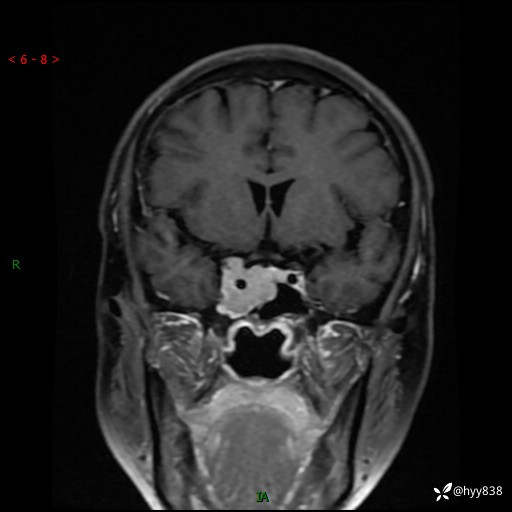

规培和研究生教学片:鞍旁占位,脑膜瘤 VS 侵袭性垂体瘤---结果公布~

现病史:患者半年前无明显诱因出现头痛头痛,呈间断性发作,无复视,无斜视,无头痛头晕,无呕心呕吐,无肢体乏力,无发作性肢体抽搐,无意识改变,无尿量增多,无体毛脱落,无色素沉着,无体重下降,无面容改变,无肢端粗大等,2024-03-26日至当地中医院住院治疗后予以对症处理(具体不详),未见明显缓解,行头颅MRI平扫检查示:“右侧蝶鞍占位,双侧上颌窦炎,双侧下鼻甲肥大,鼻中隔偏曲”,今患者为求进一步诊治来我院,门诊遂以“右侧蝶鞍占位”收住我科。 起病以来,患者精神饮食睡眠可,大小便正常。

MRI增强(外院平扫)